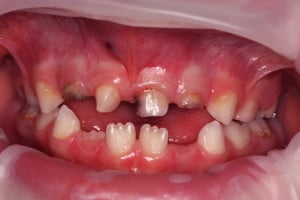

Chłopczyk w wieku 5,5 lat został skierowany przez ortodontę do placówki Stomatologia Bez Bólu z Jeleniej Góry w celu konsultacji i leczenia zaburzenia w okolicy zębów centralnych. Anomalia została wykryta na podstawie zdjęcia pantomograficznego, standardowo wykonywanego przed leczeniem ortodontycznym.

Po badaniu wewnątrzustnym stwierdzono uzębienie mieszane, adekwatne do wieku rozwojowego, bez czynnych ognisk próchnicowych. Zlecono badanie CBCT w celu dokładniejszej diagnostyki lokalizacji i liczebności przednich zębów w szczęce. W obrazie tomograficznym ukazał się od strony szczytu wyrostka, położony ząb nadliczbowy (mesiodens). Mezjodens w tym przypadku zajął miejsce stałego siekacza prawego, powodując jego dystorotacje. Usunięcia mezjodensa umożliwi wyrzniecie się zęba stałego we właściwej pozycji nie wykluczone jest wspomaganie ortodontyczne w celu ustanowieniu właściwej lokalizacji stałego zęba siecznego.